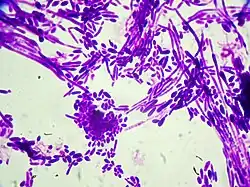

Gram stain of "Candida dubliniensis" cells (1000-fold magnification)

Gram stain of Candida dubliniensis cells (1000-fold magnification)